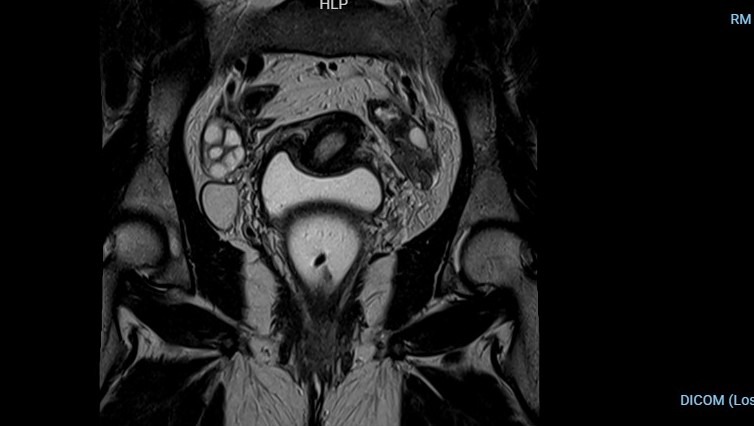

- Útero: Está desplazado, lo que dificulta el embarazo y causa molestias constantes.

- Ovarios: Están adheridos a la pared pélvica, afectando mi fertilidad y generando un dolor crónico.